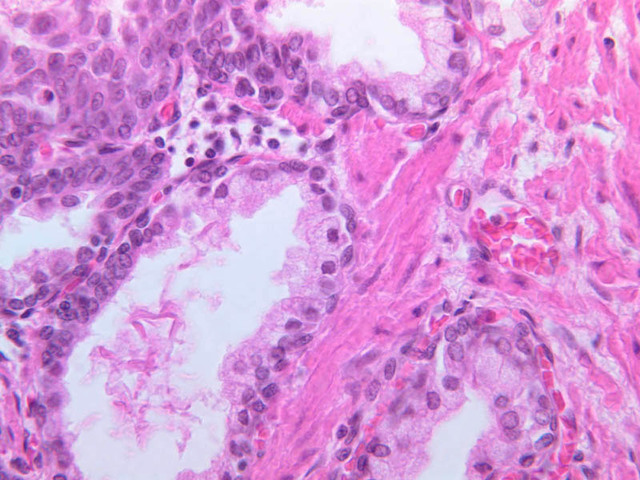

The prostate is an aggregate of numerous tubulo-alveolar glands embedded in a dense stroma of collagen fibers and smooth muscle (B-90 [2.5x, 10x, 20x, 40x-labeled]; B-91 [2.5x, 10x, [[http://www.medicalhistology.us/wiki/bin/viewfile/Main/ProstateImages?rev=1;filename=b91_prostate_adult_20x_he.jpg[20x]], 40x-labeled] [2.5x, 10x, 10x, 20x, 40x]). Note that the prostatic urethra, the portion of the urethra which runs through the prostate gland, is also present (B-91 [2.5x, 10x, 20x, 40x]). Under high dry magnification, it is obvious that the glandular epithelium varies from simple cuboidal to pseudostratified columnar. Prostatic acini often contain eosinophilic corpora amalacea (prostatic concretions) (B-90 [2.5x, 10x, 20x, 40x-labeled]). The number and degree of calcification of these spherical, lamellated structures increase with age. In some sections, the prostatic urethra can be identified. Functional, as well as morphological, maintenance of the adult prostate and seminal vesicles depends on adequate levels of circulating testosterone. Examine the prepubertal prostate (B-92 [2.5x, 10x, 20x, 40x] [2.5x-labeled, 10x, 20x, 40x]). How does this specimen differ from that on slide B-90?